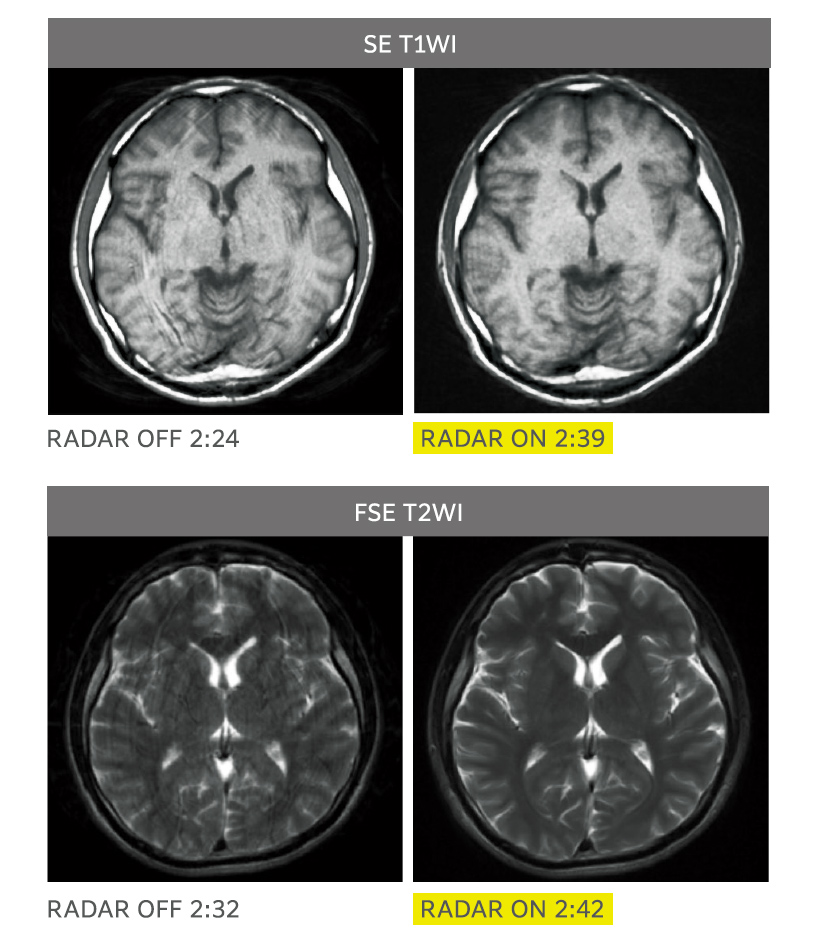

All Around RADAR

Rutin kafa incelemeleri için gerekli sekanslarda RADAR’ın kombine kullanımı

RADAR, birçok sekans, tüm alıcı bobinleri ve rastgele kesitlerle görüntüleme sırasında hareket artefaktlarını azaltarak kullanım kolaylığını artırır. RADAR, yüksek hızlı görüntüleme ile birlikte kullanılabilir. ECHELON Smart, TOF ve GrE sekanslarını destekler ve rutin baş incelemeleri için gerekli dizilerin çoğunda RADAR’ın kombine kullanımı ile uyumludur, böylece “All Around RADAR” özelliği gerçekleşir.

RADAR’ın TOF MRA ve GrE T2*WI’deki etkileri

RADAR, yüksek hassasiyetli sinyal düzeltme teknolojisi kullanılarak GrE sekanslarına uygulanmıştır. Bu, rutin baş incelemelerinde gerekli tüm sekanslar için RADAR’ın kombine kullanımını mümkün kılmıştır.